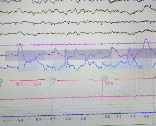

수면다원검사(Polysomnography)는 말 그대로 자는 동안 여러 생체신호를 동시 측정해서

내 수면 상태를 종합적으로 분석하는 검사예요.

| 뇌파 (EEG) | 수면 단계 분석: 얕은 수면, 깊은 수면, 렘수면 |

| 호흡 (코/입) | 무호흡, 저호흡 횟수 확인 |

| 산소포화도 (SpO2) | 산소 부족 여부 → 수면 무호흡 지표 |

| 심전도 (ECG) | 수면 중 심장 리듬 체크 |

| 안구·턱·다리 근전도 | 이갈이, 하지불안증후군 여부 |

| 코골이 소리 | 강도 및 진동 패턴 |

잠자는 동안 몸의 상태를 통째로 녹화하고 분석하는 것이라고 보면 돼요.

특히 수면 무호흡증 진단의 ‘골드 스탠다드’ 검사입니다.